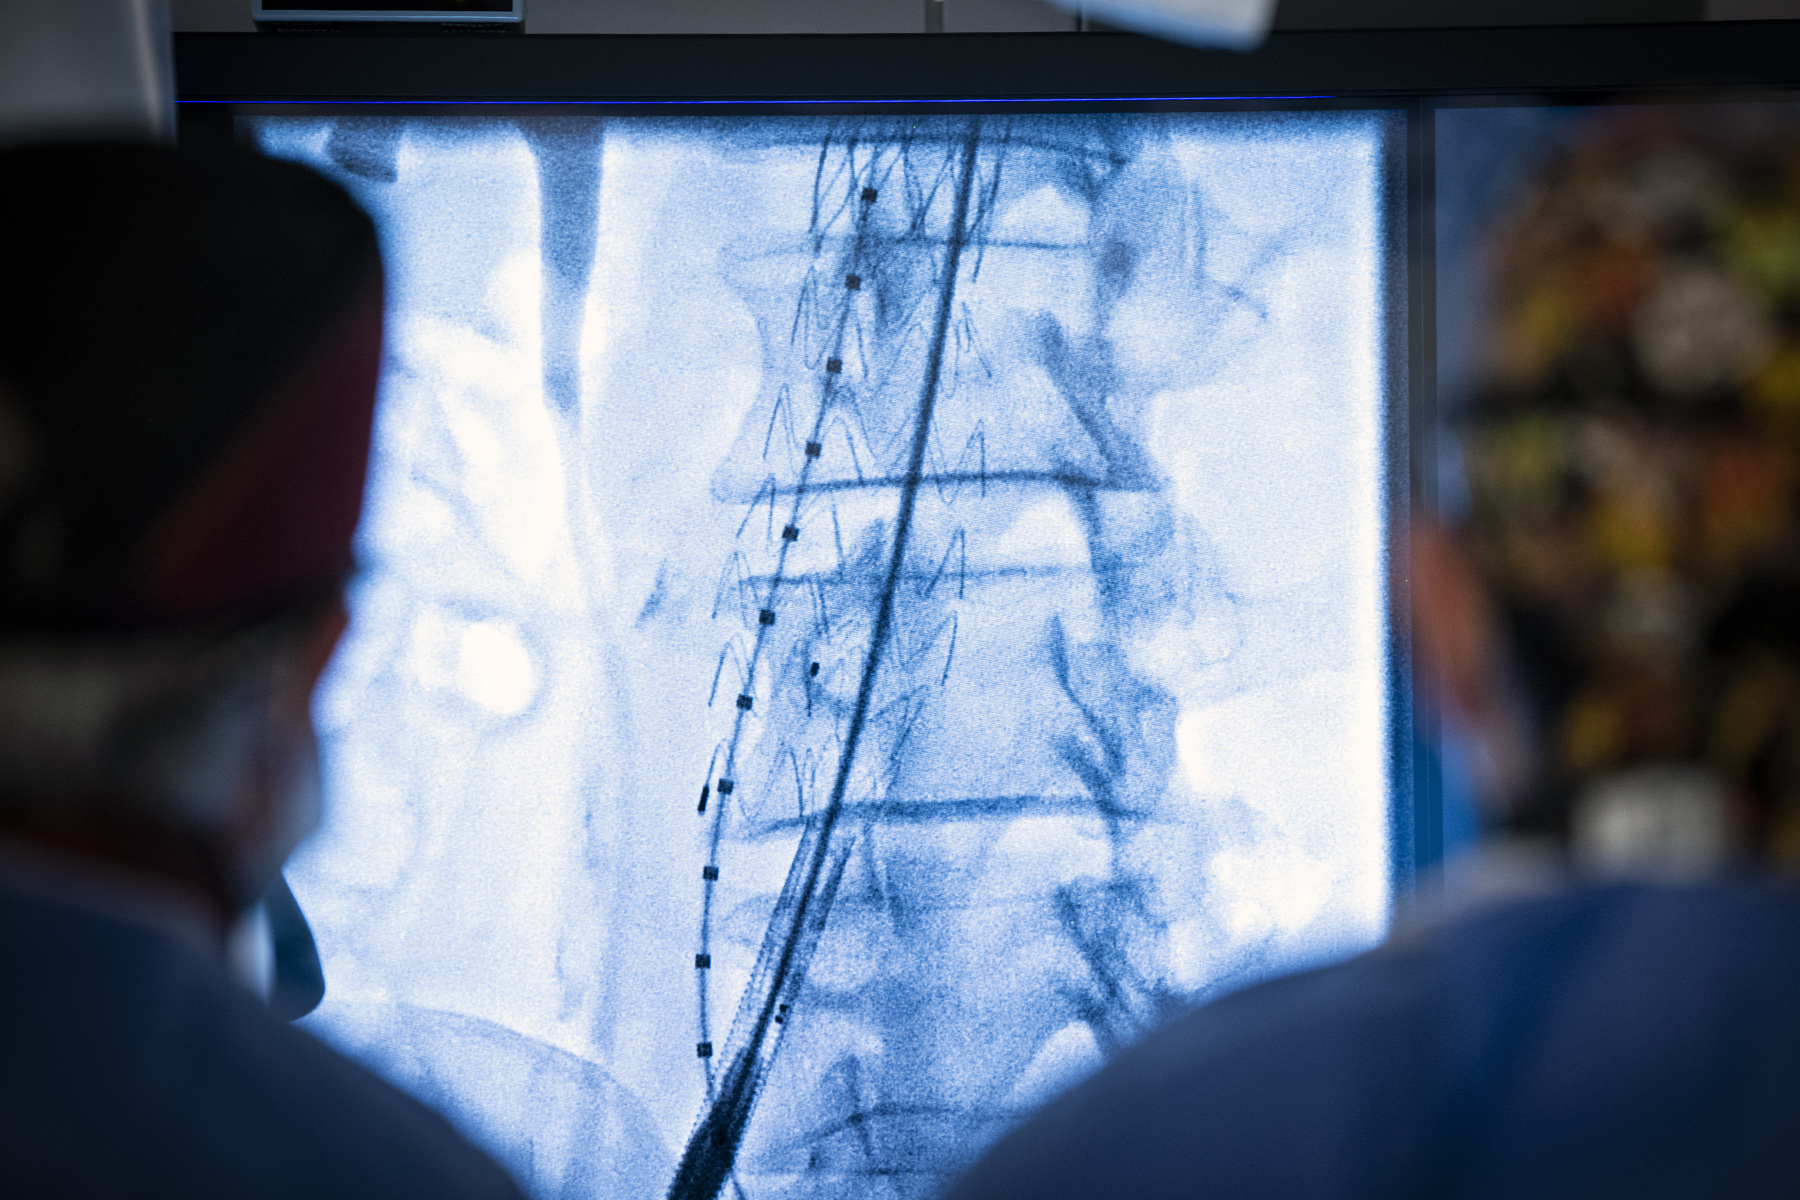

Instead of opening up the chest or abdomen in order to access the aorta, an EVAR is a minimally-invasive procedure in which medical teams insert a long tube carrying a stent graft (a metal mesh tube covered with fabric) into the main artery in the thigh and guide it to the area of the aorta with the aneurysm. Once placed, the stent graft works to restore normal blood flow and prevent the aneurysm from growing or bursting, which could cause life-threatening internal bleeding.

Multidisciplinary team (including nurses, vascular surgeon, interventional radiologist, interventional radiology technologist, and anesthesiologist) performing an endovascular repair of an aortic aneurysm in the new hybrid operating room.